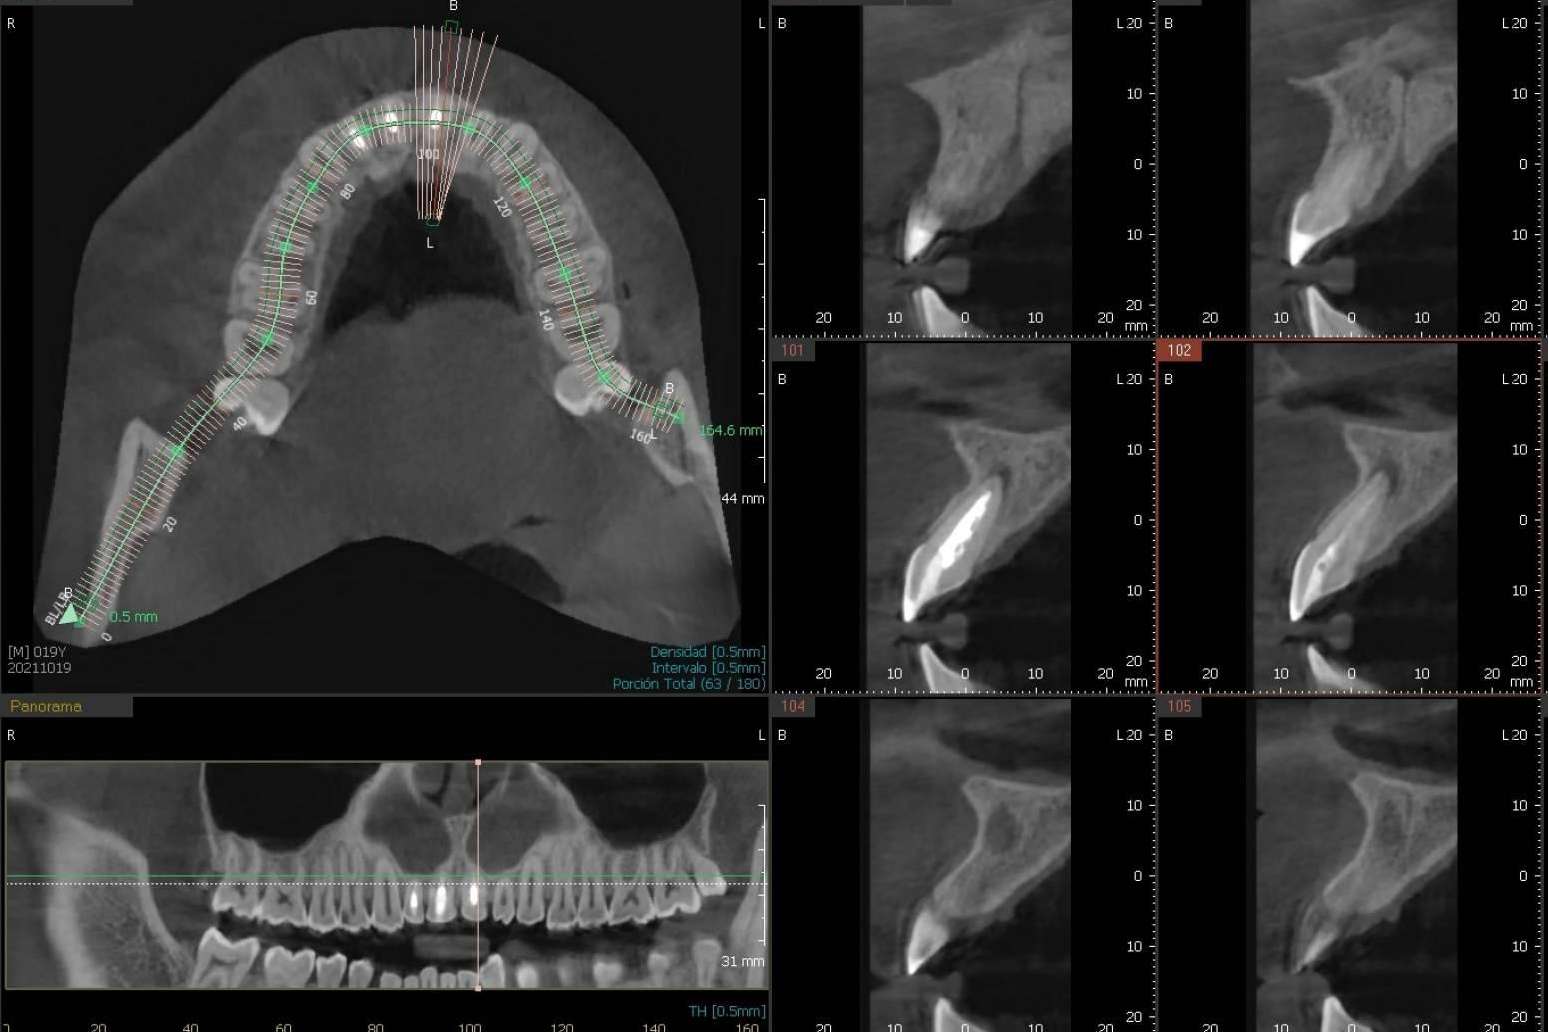

El CBCT dental se diferencia de otros tipos de radiografías dentales porque ofrece una representación más clara, fiel y tridimensional de la estructura dental y resto de maxilares de una persona. Es precisamente su tridimensionalidad la que permite al especialista poder tener una mejor visualización del área, por ejemplo, a nivel inferior, superior, anterior, frontal, etc.

Además, ofrece diferentes niveles de ampliación, con lo cual se logra una visualización muy precisa, entregando una imagen de gran calidad.